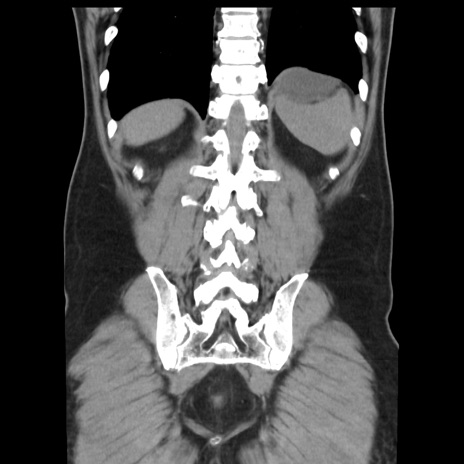

症例16(冠状断像)

【症例】 70歳代男性

【主訴】 腹痛、嘔吐

【現病歴】 約1ヶ月前より間欠的に腹痛と嘔吐あり、当院消化器内科を受診したところCTで多発する肝臓のLDAを指摘され、精査中であった。以降は消化器症状は安定していたが、2日前より嘔気と腹痛があり、同日より排便・排ガスが消失した。改善認めず、 本日、救急外来を受診した。

【既往歴】 大腸ポリープ切除後。

【身体所見】意識清明・会話良好、BT 36.3℃、BP 127/80mmHg、 P 80bpm、腹部:膨満あり、平坦・軟、上腹部正中および下腹部正中に圧痛あり、反跳痛なし、筋性防御なし。

【データ】WBC 7200、CRP 0.77